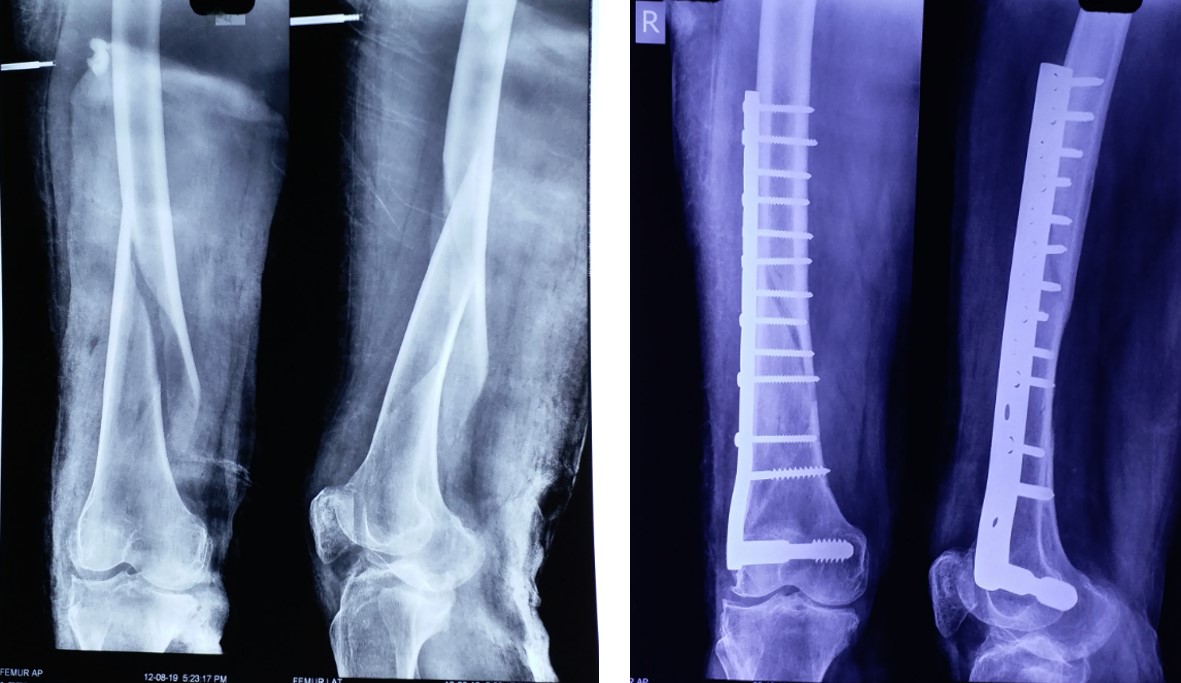

Femer

AVN